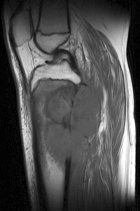

13 year old male presents with c/o R knee pain, which he attributes to an unknown injury suffered two months prior to initial evaluation.

Zoom image: Radiological image Radiological image.